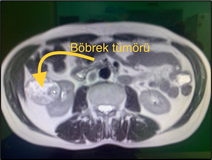

Böbrek kanseri tanısının temeli görüntüleme yöntemlerine dayanmaktadır. BT veya manyetik rezonans (MR) görüntüleme ile karın bölgesinin enine kesitsel filmleri alınır ve bu filmlerde böbrek kanserinin böbrekteki yeri ve diğer organlarla ilişkisi ortaya konur. Bu sırada eğer hastanın böbrek fonksiyonları normalse, damardan dokuları boyayan bir madde verilerek böbrek tümörünün belirginleşmesi sağlanır. Böbrek fonksiyonu iyi olmayan veya boyalı maddeye alerjisi bulunan hastalarda ise BT yerine MR görüntüleme kullanılır. Çoğunlukla bu aşamada hastalığın herhangi bir organa sıçrayıp sıçramadığı kemik sintigrafisi veya FDG PET-CT ile ortaya konulduktan sonra böbrek kanserinin klinik evrelemesi yapılır. Diğer kanser türlerinin aksine biyopsi böbrek kanserlerinde nadiren; örneğin arada kalınan vakalarda veya küçük tümörlerde hastaya yaşından veya ek hastalıklarından dolayı yalnızca takip önerilecekse, gerekli olmaktadır.

Şekil: Sağ böbrekten kaynaklanan bir böbrek tümörü